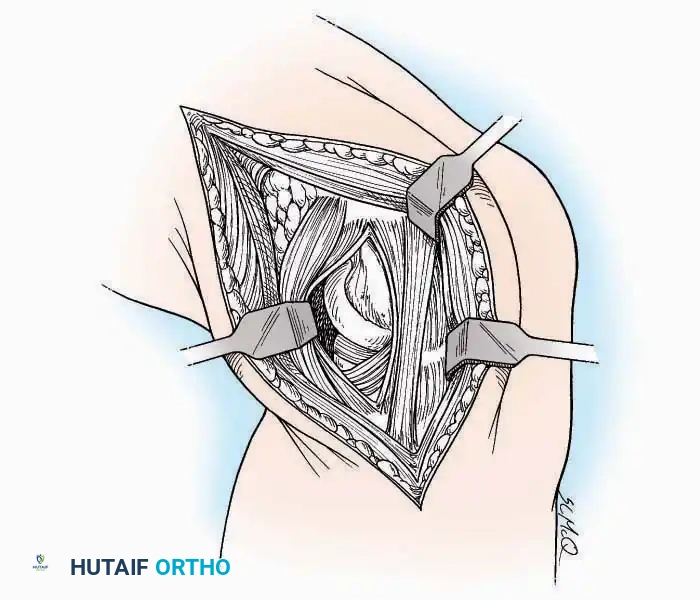

Medial Approach

Indications: Hallux valgus correction (bunionectomy), first MTP arthrodesis, or cheilectomy.

Surgical Technique:

* Incision: Make a curved incision 5 cm long on the medial aspect of the joint. Begin just proximal to the IP joint, curve it over the dorsum of the MTP joint (medial to the extensor hallucis longus [EHL] tendon), and terminate on the medial aspect of the first metatarsal 2.5 cm proximal to the joint.

* Superficial Dissection: As the deep fascia is incised, identify and laterally retract the medial branch of the first dorsal metatarsal artery and the medial branch of the dorsomedial nerve (a terminal branch of the superficial peroneal nerve).

* Deep Dissection: Dissect the fascia from the dorsum down to the bursa overlying the medial eminence of the metatarsal head.

* Capsulotomy: Make a curved incision through the bursa and joint capsule. Begin dorsomedially, continue proximally dorsal to the metatarsal head, sweep plantarward, and end distally on the medioplantar aspect of the joint. This creates an elliptical, racquet-shaped flap attached at the base of the proximal phalanx.

⚠️ Surgical Pitfall

While distal reflection of this racquet flap provides ample exposure of the first MTP joint, the extensive subfascial undermining required can compromise the vascularity of the skin flap, leading to delayed healing or necrosis. Consequently, the dorsomedial approach is often preferred in modern practice.